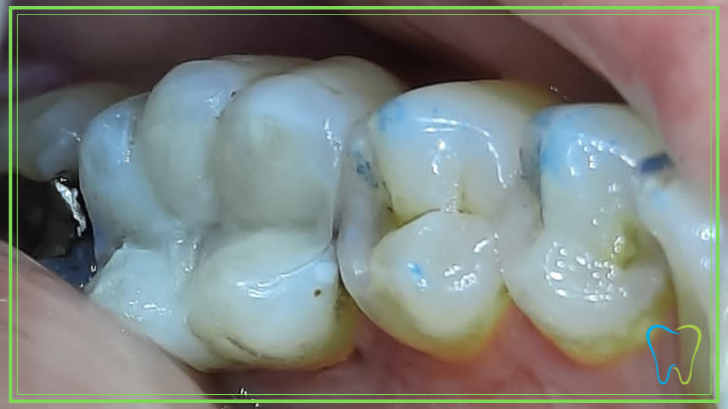

Le otturazioni estetiche in composito, rappresentano quanto di meglio si possa realizzare per ricostruire un elemento dentario.

Il materiale composito è assolutamente sicuro, biocompatibile e duraturo nel tempo.

Nel caso di un otturazione in amalgama dentale, il dente può essere completamente ricostruito recuperando il suo colore originale ed estetico.

Eventuali ombre scure e pigmentazioni possono essere contrastati grazie all’utilizzo di super colori, realizzati proprio a tal scopo dalle case produttrici.

I materiali compositi sono perfettamente biocompatibili e durevoli nel tempo, resistendo ad ogni tipo di stress masticatorio.